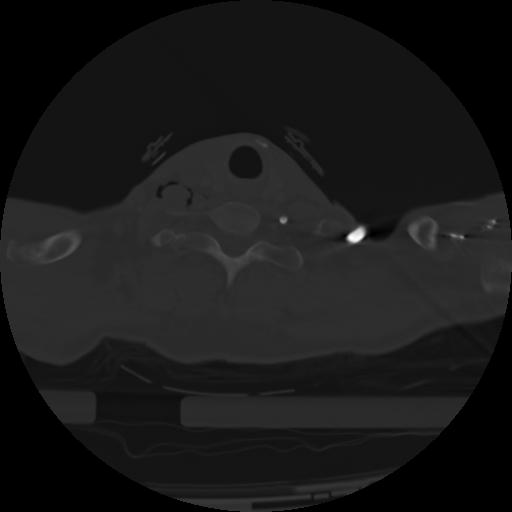

21 ANGIO,CE,Axial,3.0,ANGIO,,